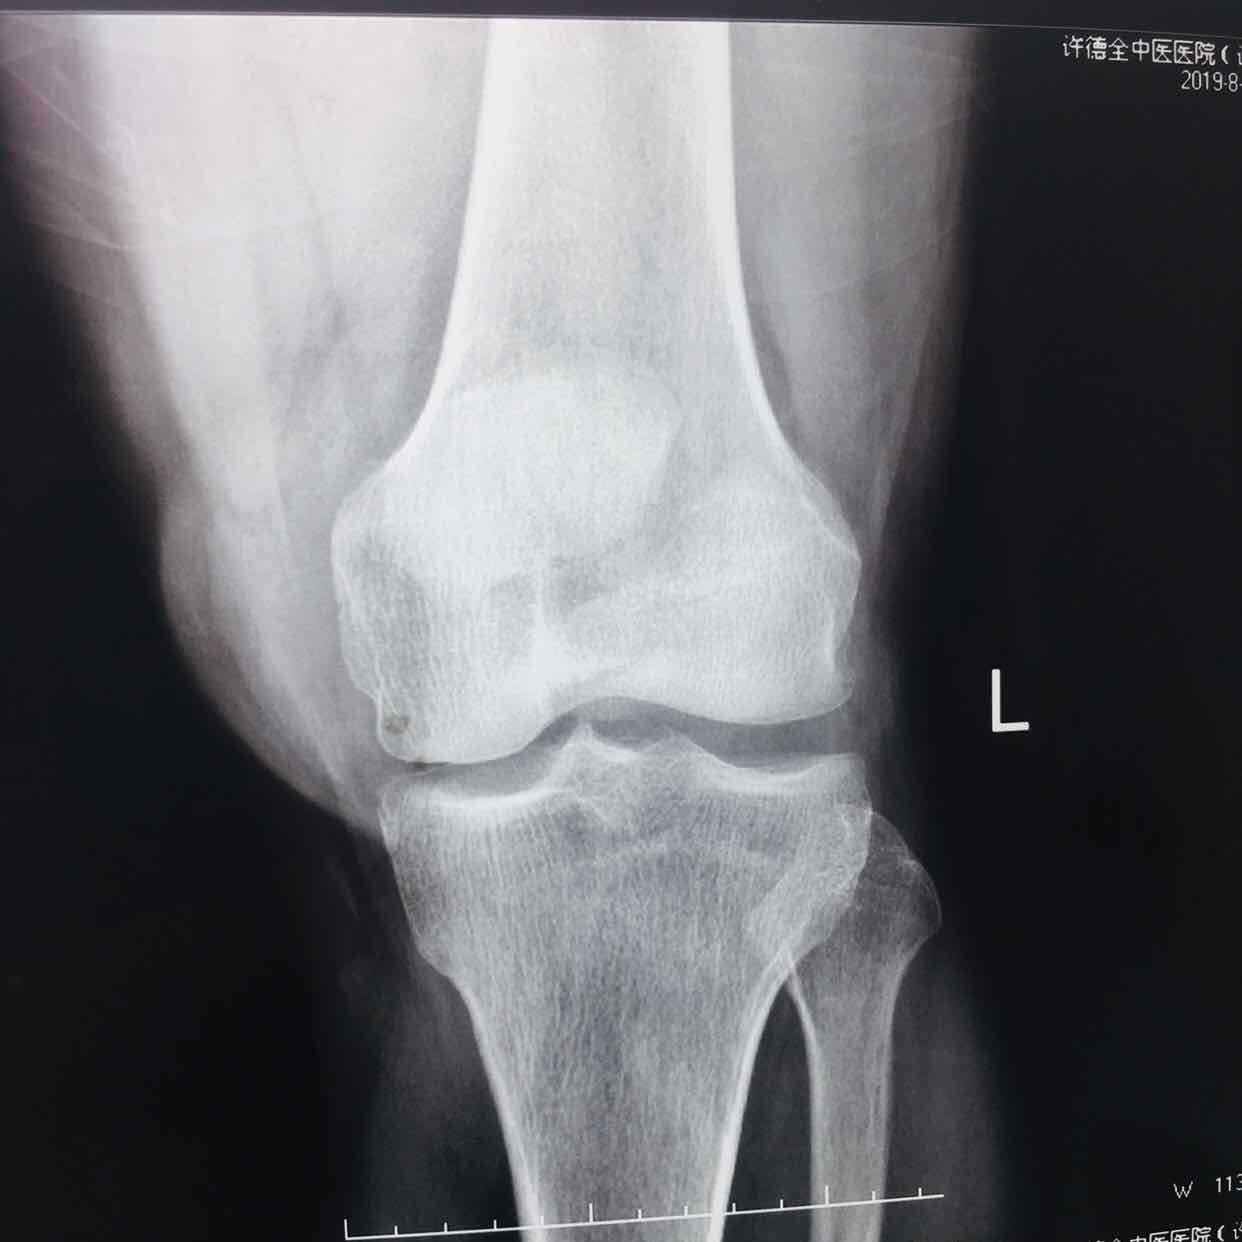

髌骨粉碎性骨折(髌骨爪➕克氏针固定)

摔伤后左膝部肿痛,活动受限1小时入院。既往身体健康,无特殊不良嗜好。

生命体征平稳,心肺复未见异常。左膝部肿胀明显,皮色发红,皮温高,压痛明显,可及骨折断端,伸膝关节受限,末梢血运感觉正常。

诊断左髌骨粉碎性骨折在腰麻下行切复内固定术,术后抗炎,消肿止痛等处理。